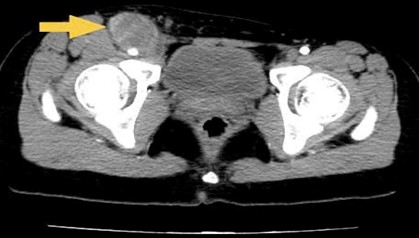

- CT ổ bụng có tiêm thuốc cản quang: Gan:  Kích thước bình thường, bờ đều. Nhu mô đồng nhất trước và sau tiêm thuốc cản quang. Không thấy khối khu trú.

Hình 3: Nhu mô gan hạ phân thuỳ IV có ổ ngấm thuốc kém kích thước ~ 25x7mm. ( mũi tên vàng) nay đã mất

Vùng bẹn phải, nằm dọc bó mạch chậu ngoài và đùi chung có hình ảnh khối kích thước 32x68mm

Hình 4: Khối lớn vùng bẹn phải thay đổi kích thước không nhiều ( mũi tên vàng)